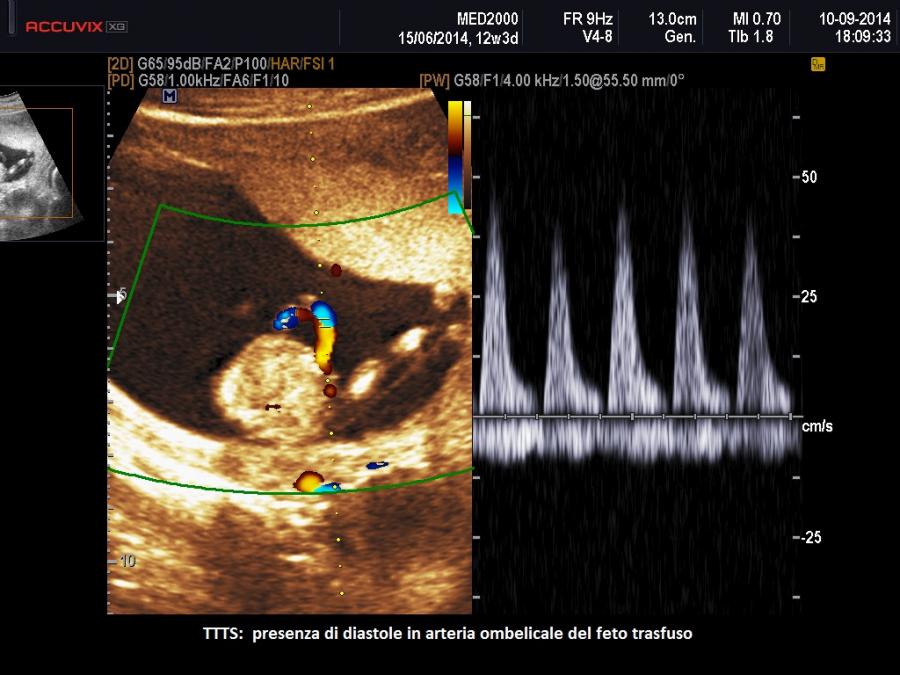

Quando il delicato equilibrio tra i vasi sanguigni dei due gemelli viene meno si verifica la malattia. La sindrome TTTS è caratterizzata dal passaggio anomalo di sangue e di sostanze vasoattive attraverso le anastomosi da un gemello (definito donatore) all’altro (definito ricevente). Lo squilibrio emodinamico che ne deriva comporta un aumento del volume di liquidi nel gemello ricevente con aumento del precarico dimostrato da un flusso venoso ombelicale più elevato (Yamamoto M. et al., 2007), che provoca aumento di volume delle camere cardiache con rilascio del peptide natriuretico atriale e cerebrale cui segue un aumento della diuresi e conseguente polidramnios (Van Mieghem T. et al, 2010; Habli M. et al, 2010). Inoltre aumenta la produzione di endotelina, un potente vasocostrittore, con conseguente ipertensione del ricevente ed ipertrofia cardiaca e rigurgito valvolare (Habli M. et al, 2010; Bajoria R. et al, 1999). Di converso nel gemello donatore si ha ipovolemia e successivamente una ridotta produzione di urina con conseguente oligoidramnios e riempimento vescicale minimo o assente. In risposta si verifica una sovraregolazione del sistema renina-angiotensina che passa al ricevente ipervolemico attraverso la circolazione condivisa amplificando l’ipertensione e la cardiomiopatia (Mahieu-Caputo D. et al, 2005; Galea P. et al, 2008).

La visualizzazione della vescica e la valutazione della flussimetria Doppler del cordone ombelicale e del dotto venoso in entrambi i feti permette di definire lo stadio di evoluzione della patologia che viene distinta in 5 stadi (Quintero R. et al, 1999):